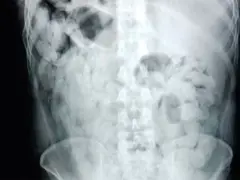

Ante la urgencia médica, los pasajeros fueron trasladados de inmediato al hospital de Trancas, donde las placas radiográficas confirmaron la presencia de múltiples cuerpos extraños en sus organismos. Bajo supervisión médica, ambos lograron evacuar 180 cápsulas que fueron sometidas a análisis de campo.